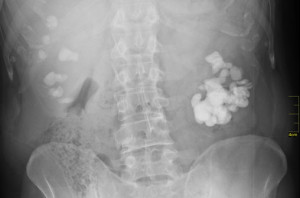

Böbrek Taşı Teşhisi - Prof. Dr. Sinan Zeren